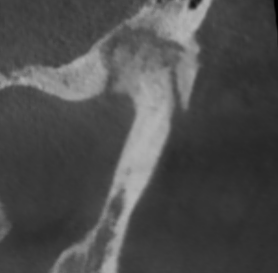

У здорового височно-нижнечелюстного сустава суставные поверхности гладкие и ровные. Такие суставы, как правило, восстанавливаются быстро.

Но, ко мне приходят пациенты с изменёнными суставными поверхностями в виде артроза. Эти суставы повреждены, и в них нарушено нормальное вращение.